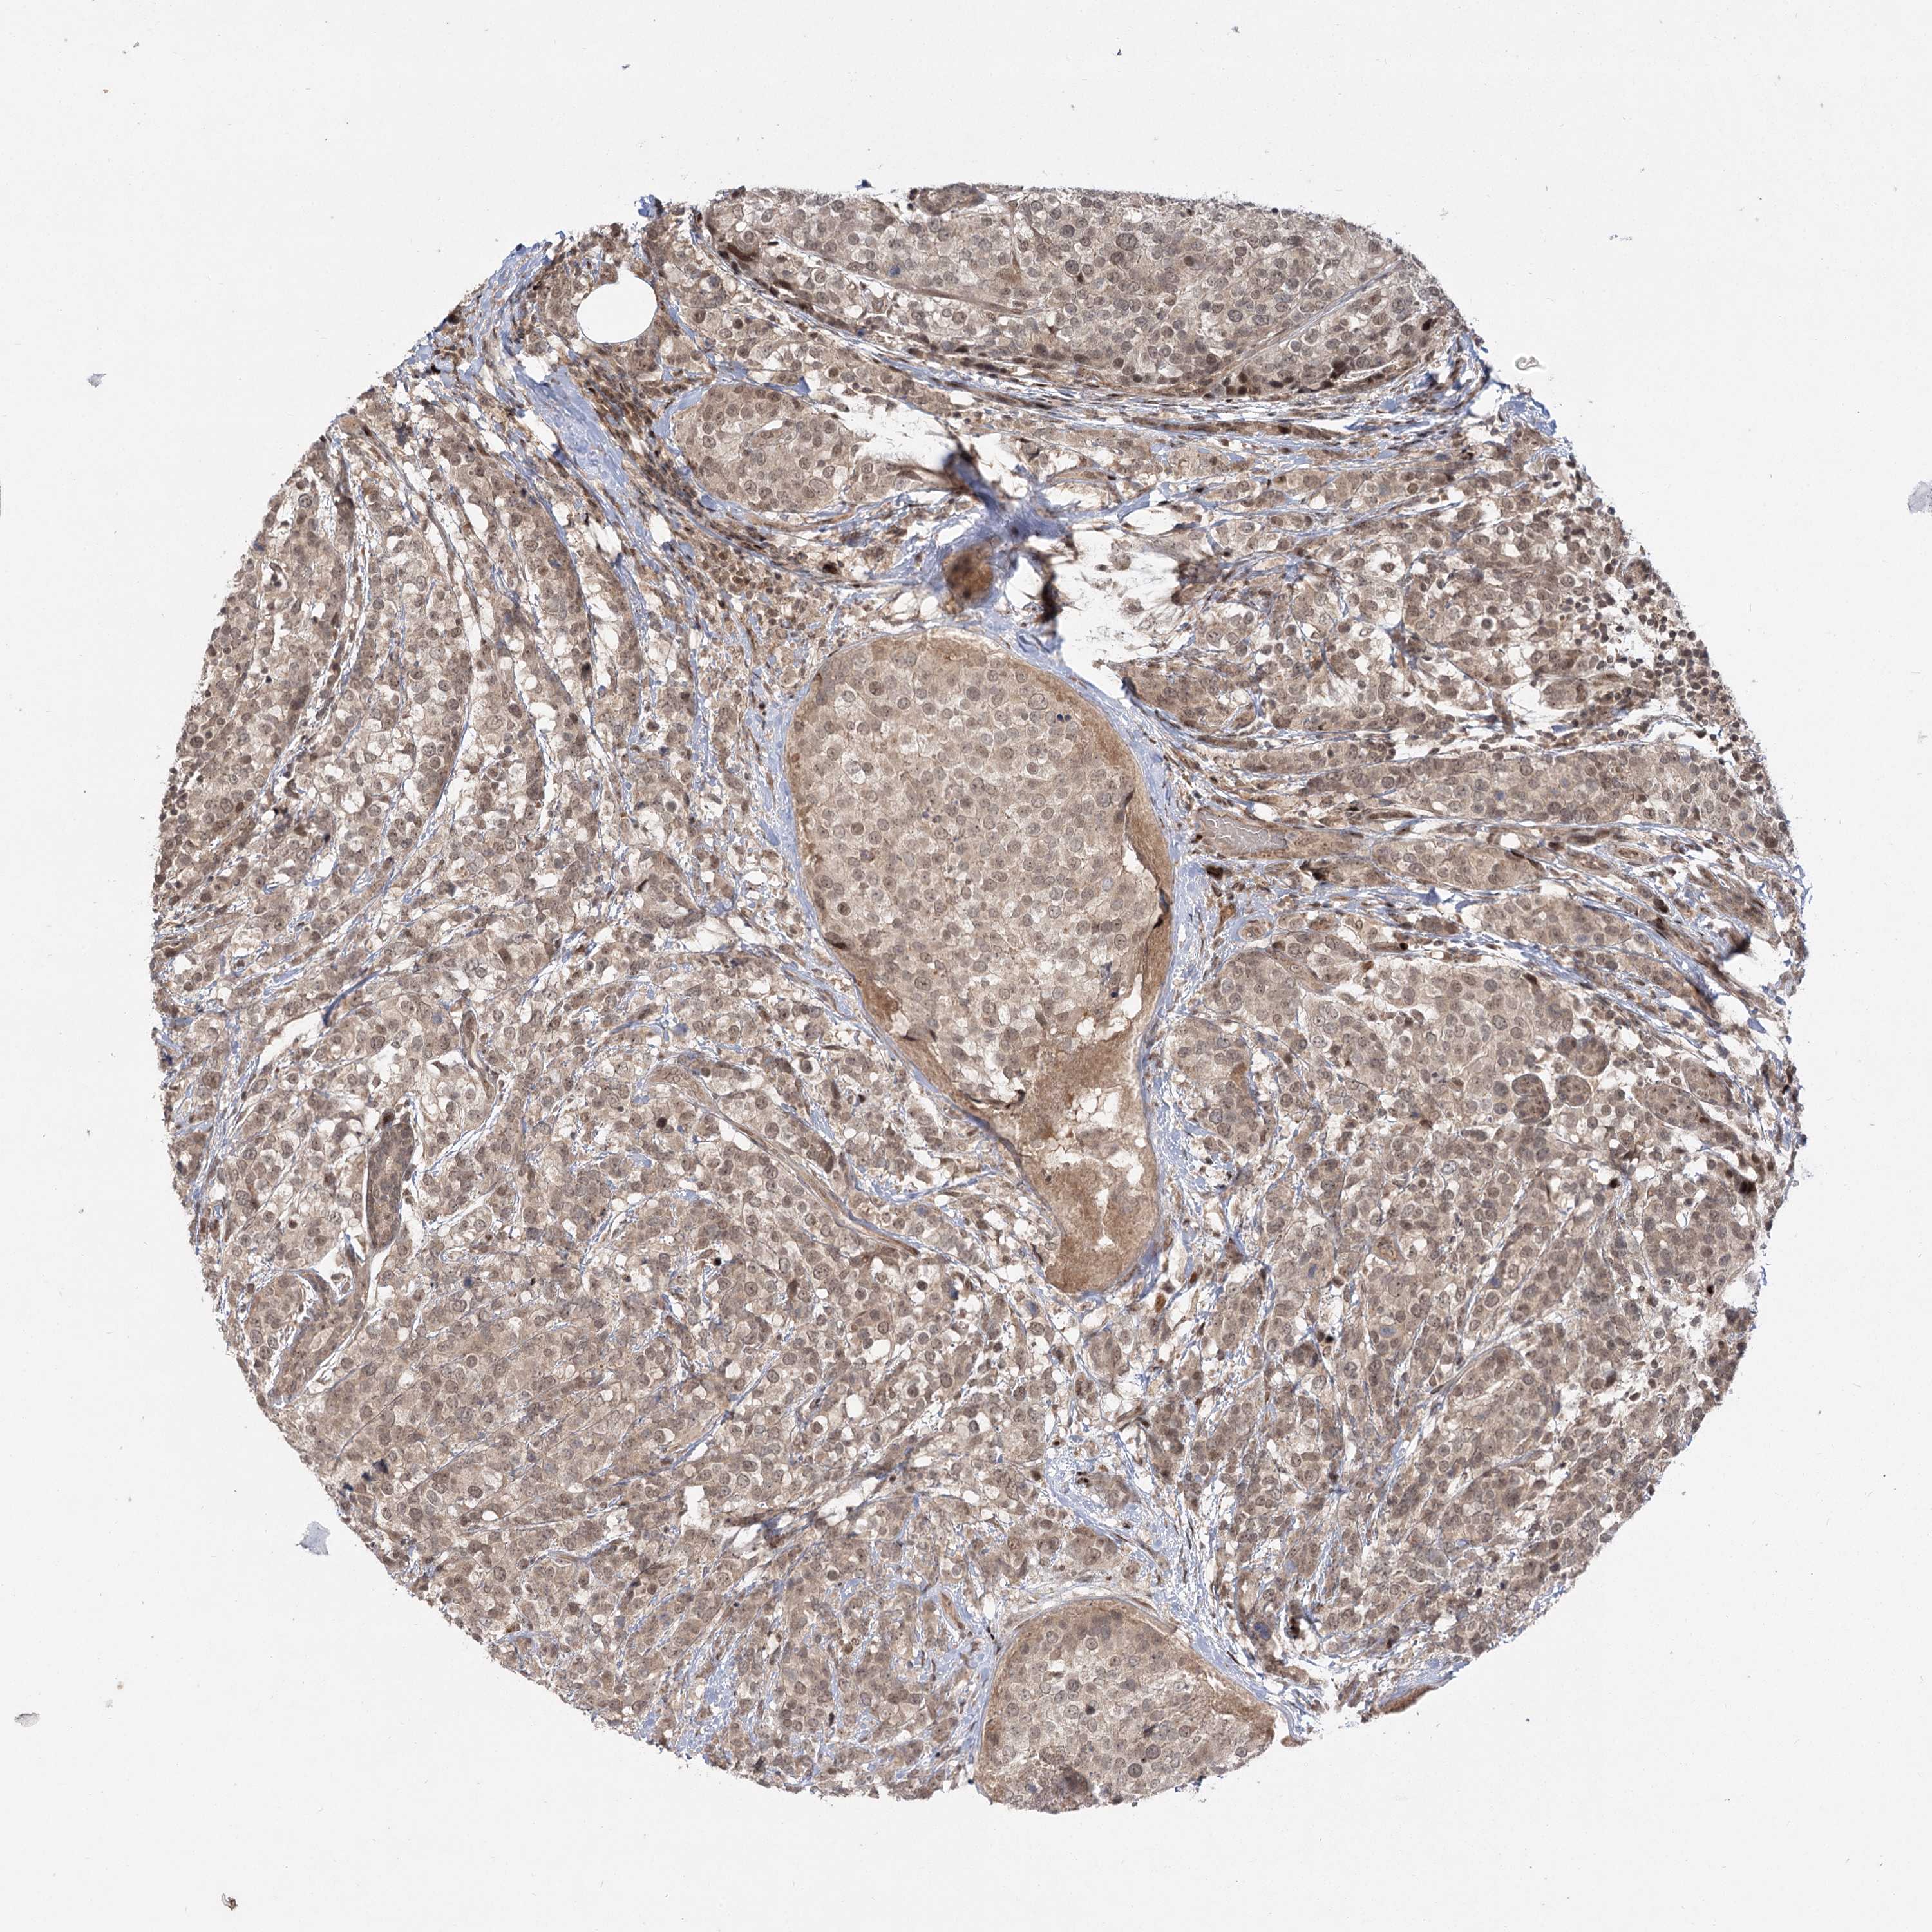

BRCA TCGA BRCA VALIDATION PROTEIN EXPRESSION

Breast cancer

Human cancer